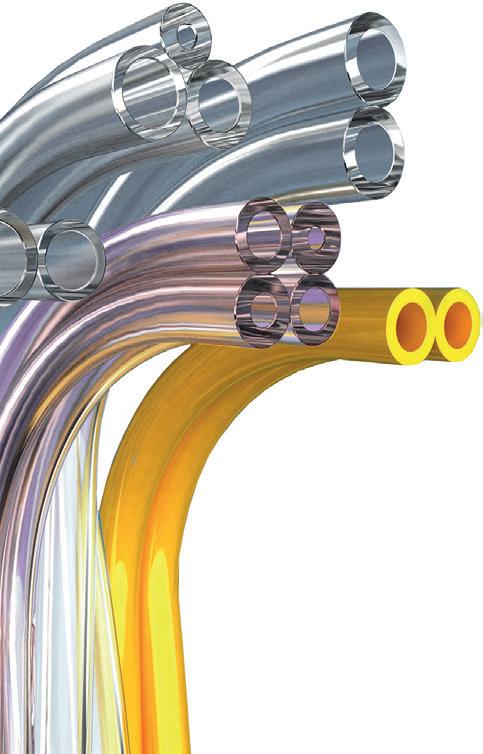

Coextruded tubing has a minimum internal diameter of up to only 0.1 millimeter and is indispensable in many drug delivery systems. Depending on the application, it may have layers introduced during manufacturing — a process known as composite tubing extrusion — to improve the functionality and safety of the injection system. Here, the outer layer connects the coextruded tubing to other components of the fl uid outlet such as the needle insertion system, reservoir or pump unit. The tubing and all connecting joints must withstand pressure of up to six bar. The inner layer is inert, thereby ensuring marginal interaction with the drug throughout the product’s life cycle. Properties like these make coextruded tubing an important component of the fl uid outlet, the heart of any drug delivery system. Raumedic not only designs and adapts the tubing for individual systems, it also intelligently combines various manufacturing processes.

MIXING AND MATCHING Many medical devices must incorporate multiple single-use tube lines, each of which supplies or removes a diff erent fl uid or gas. In addition, some of these devices also require a separate power line to provide a light source. A paratube makes it possible to combine these tubes into a single structure that is signifi cantly easier for clinicians to manage. In this landscape, versioning is the surest path toward safety and success. To minimize risk during medical procedures requiring multiple lines to deliver fl uids, gases, suction and power to the same application space, a custom design may be recommended or even necessary to best ensure proper line connections. Tubes can be composed of diff ering compounds engineered to accommodate the fl uid, gas or suction it provides, and tube ends can be separated to ensure effi cient and secure bonding into connecting ports. Some advanced tubing manufacturers, such as TekniPlex Healthcare, can even produce confi gurations of up to eight tubes in eight distinct colors, bonded together in a single device solution. But of course, matching the right tubes to the right ports isn’t the only challenge associated with paratubes. Several other pitfalls may arise far upstream from patient care, in the production and inspection processes.